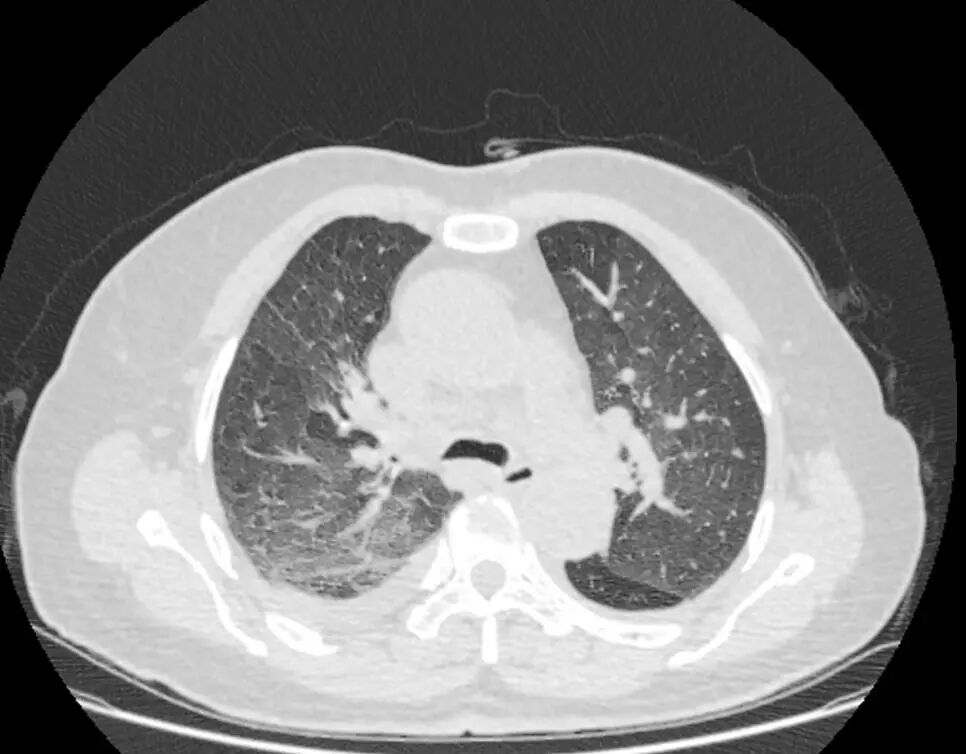

2023-05-06起予DPD方案化疗2程后病情持续进展,血象持续低下,化疗期间反复肺部感染,痰和支气管镜检肺泡灌洗液mNGS多次检出新冠病毒(XBB型)、鲍曼不动杆菌、韦荣球菌、耶氏肺孢子菌、EB病毒等。经积极抗感染后好转。